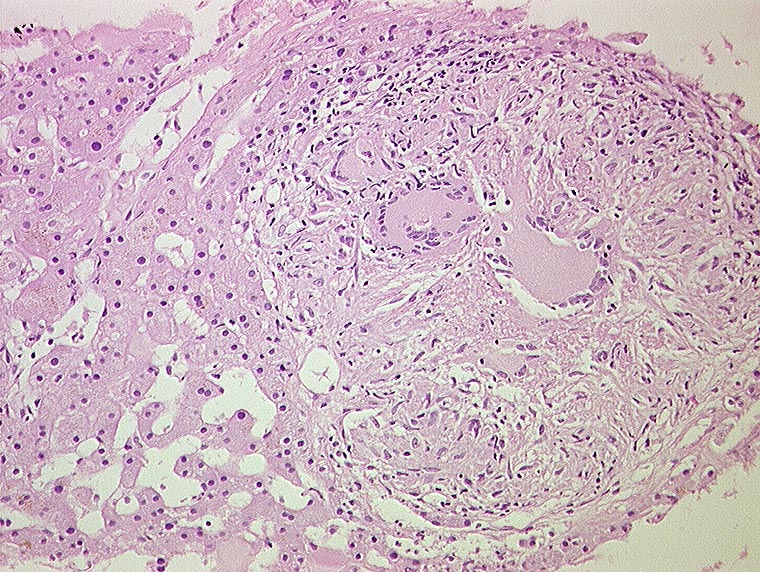

AP/ Miliartuberkulose der Leber

Miliartuberkulose der Leber

Entzündung infektiös

Leber, Gallenwege, Pankreas

Leber